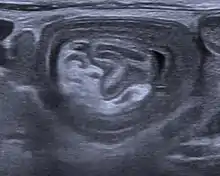

An intussusception is often suspected based on history and physical exam, including observation of Dance's sign. A digital rectal examination is particularly helpful in children, as part of the intussusceptum may be felt by the finger. A definite diagnosis often requires confirmation by diagnostic imaging modalities. Ultrasound is the imaging modality of choice for diagnosis and exclusion of intussusception, due to its high accuracy and lack of radiation. The appearance of target sign (also called "doughnut sign" on a sonograph, usually around 3 cm in diameter, confirms the diagnosis. The image seen on transverse sonography or computed tomography is that of a doughnut shape, created by the hyperechoic central core of bowel and mesentery surrounded by the hypoechoic outer edematous bowel.[11] In longitudinal imaging, intussusception resembles a sandwich.[11] It is also called "pseudokidney" sign because hyperechoic tubular centre is covered by a hypoechoic rim producing a kidney-like appearance.[12]